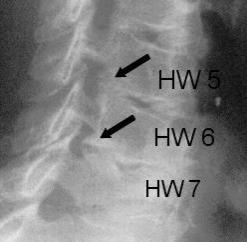

Durch die Untersuchung und Anamneseerhebung ergeben sich wichtige Hinweise auf die Ursachen der Beschwerden. Hieran orientiert sich auch maßgeblich die Empfehlung für oder gegen eine Operation. Ergänzend sind häufig konventionelle Röntgenaufnahmen sowie eine Kernspintomographie sinnvoll. Knochenveränderungen werden besser mit der Computertomographie erfasst. Besteht der Verdacht auf eine Rückenmarkserkrankung oder eine Störung der Nervenfunktion wird eine elektrophysiologische Untersuchung (evozierte Potentiale) organisiert. Hierbei wird, ähnlich wie bei einem Stromkabel, die Durchgängigkeit der Nervenbahnen gemessen.

Anders als an der unteren Wirbelsäule kann nur selten vom Nacken (dorsal) aus operiert werden, da das Rückenmark im Weg ist. Dieses ist nur möglich, wenn der Bandscheibenvorfall seitlich des Rückenmarks liegt. In den meisten Fällen wird jedoch von vorne (ventral) operiert.

Operation der Halswirbelsäule von ´hinten´:

Geeignet für dieses Operationsverfahren sind Patienten, bei denen es durch degenerative Veränderungen zu einer isolierten Verengung eines Wurzelkanales bzw. des Wurzelaustrittsloches gekommen ist. Ein relevanter Bandscheiben-Vorfall muss hierbei nicht vorliegen, am geeignetsten ist die isolierte, knöcherne Wurzelkanal-Verengung.

Der Eingriff wird in Vollnarkose und Bauchlagerung mit Überstreckung von Kopf- und Halswirbelsäule durchgeführt. Nach sorgfältigem Ablösen der sehr kräftigen Nackenmuskulatur von den hinteren Anteilen der Halswirbelsäule wird unter Röntgenkontrolle die richtige Etage verifiziert. Anschließend werden von hinten mit Mikrofräsen und Stanzen die aneinander grenzenden seitlichen Anteile der Wirbelhalbbögen entfernt. Der geschaffene, knöcherne Defekt ist in aller Regel kleiner als ein Fingernagel und verhilft dem Patienten zur Beschwerdefreiheit.